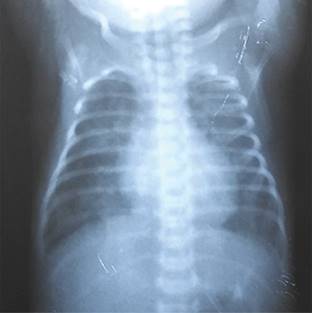

Durante la VS, la paciente mantuvo oxigenación adecuada, lo que permitió disminuir progresivamente la FiO2 y PMA. En total, la ventilación monopulmonar tuvo una duración de 48 h; después el tubo endotraqueal se colocó en posición correcta para ventilar ambos pulmones, observándose resolución total del EPI (Figura 3). Durante más de una semana estuvo con VM sin que presentara recurrencia del evento.